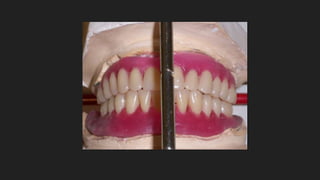

Maxilar Superior: 8

implantes bien

distribuidos para

soportar bien las

fuerzas de la

mordida y

masticar bien.

Maxilar Superior: 8 implantesbien distribuidos para soportar bien las fuerzas de la mordida y masticar bien.